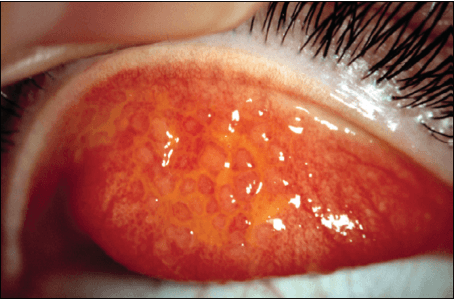

巨乳突結膜炎 或者 異物相關乳突結膜炎

照片由香港理工大學眼科視光學院提供